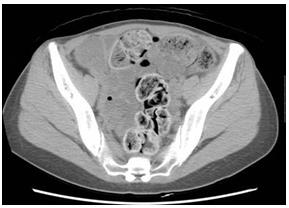

照片4:腹部CT 照片,軸向圖像,盆腔

盆腔左邊的降結(jié)腸中含氣體,看似軟便。腹壁中間為乙狀結(jié)腸,發(fā)白,水分較少,猶如石塊。仙骨前面的直腸存在類(lèi)似兔子糞便樣的小結(jié)石狀糞便。

照片6:腹部CT

乙狀結(jié)腸出現(xiàn)明顯擴(kuò)張,2周的糞便鑲嵌其中。乙狀結(jié)腸上部將肝下方,胃和橫結(jié)腸向上方擠壓,左側(cè)乙狀結(jié)腸下方可確認(rèn)內(nèi)腔積蓄圓形糞便和氣體。